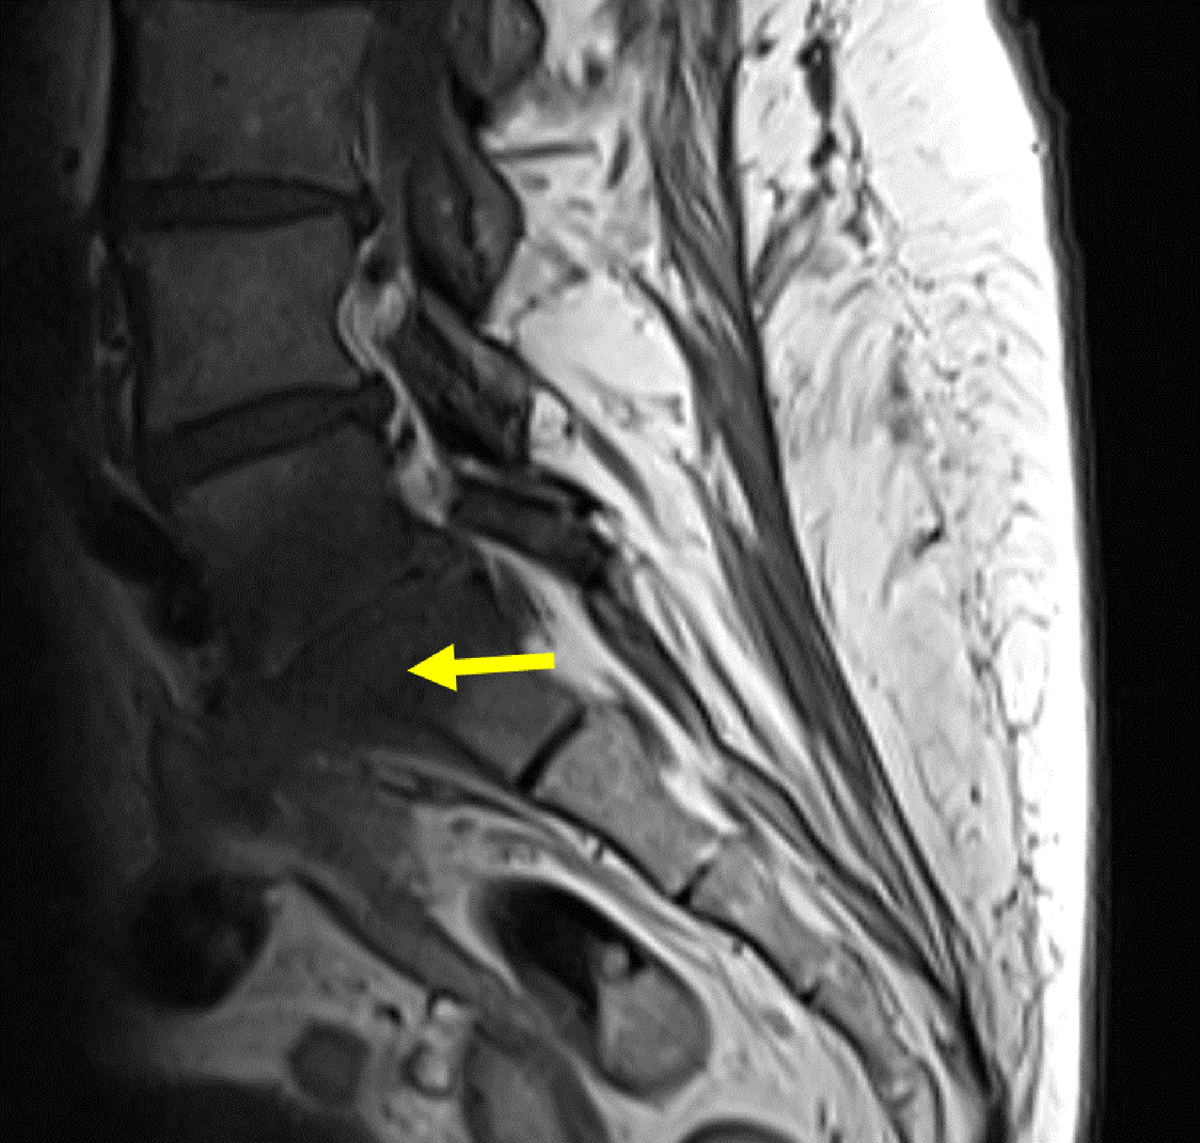

Figure 7

Sagittal contrast MRI in T1 fat saturation weighing: Full path of fistula from L5-S1 (yellow arrow) to the vagina. The fistula (red arrow) presents with a hyperintense wall surrounding a hypointense lumen.